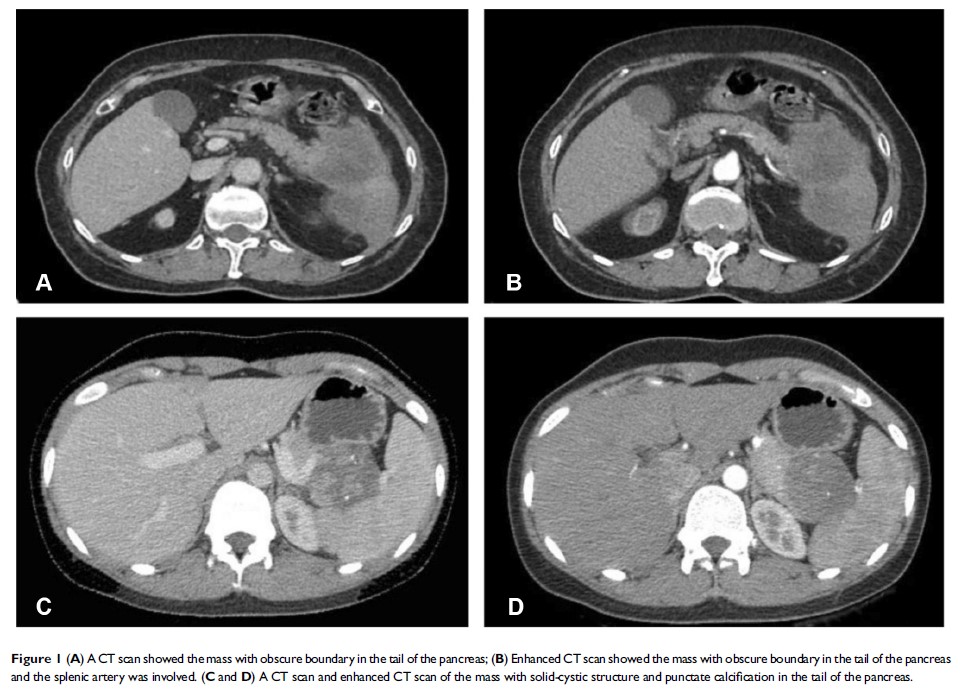

胰腺实性假乳头状瘤的诊断、外科治疗和病理学发现:一个单中心经验